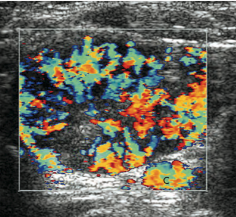

• *Hypoechoic solid lesion**

• Homogeneous

• Oval (~1cm)

• *Hypervascular**

• Arch

• Feeding vessel